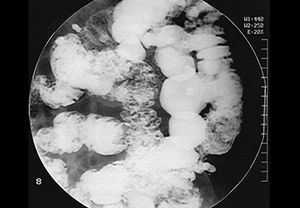

- ирригоскопия — рентгенологическое исследование кишечника с предварительным его наполнением контрастным веществом;